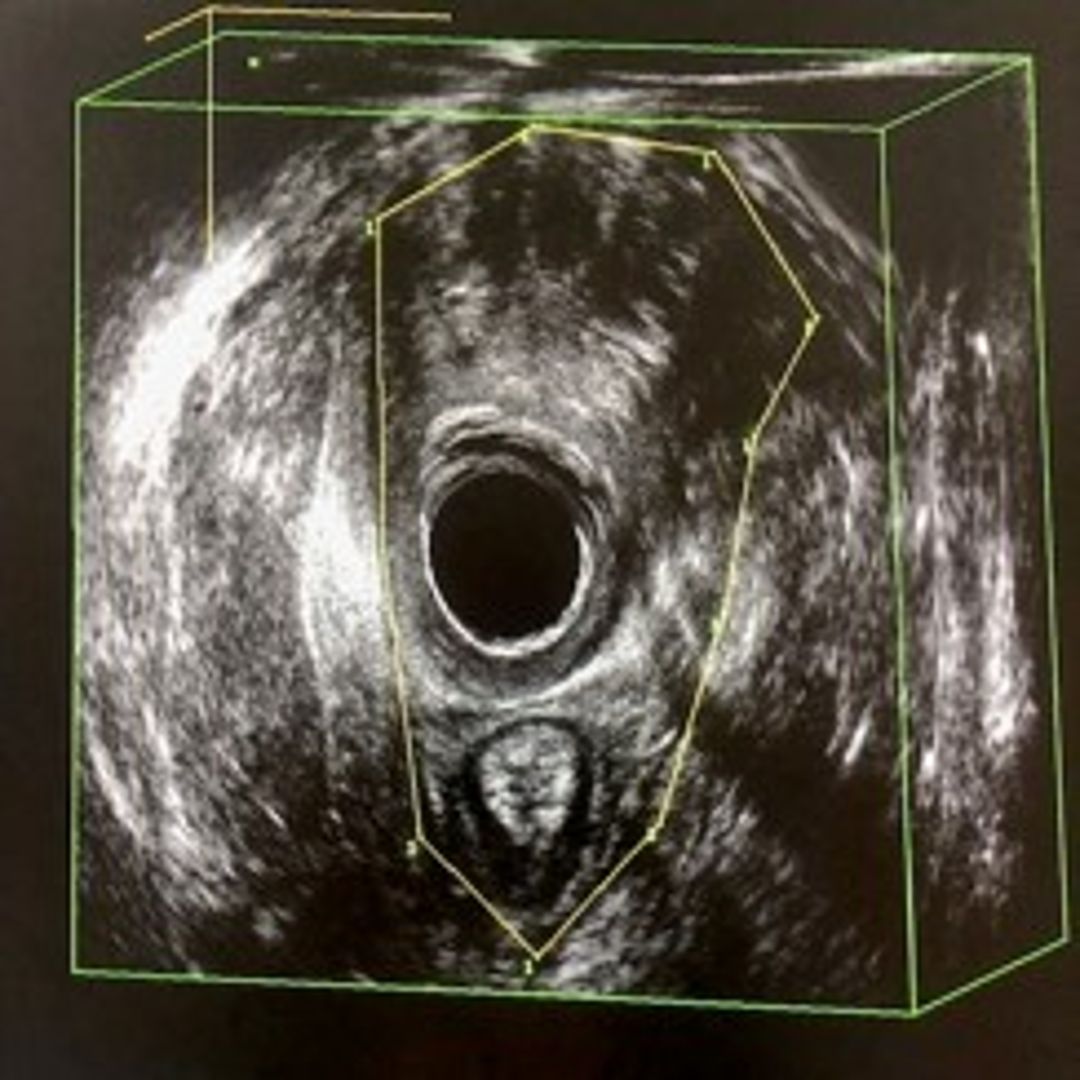

A pelvic floor ultrasound with a 3D transvaginal probe was performed for an objective evaluation of the urogenital hiatus area and the possible presence of partial muscle lesions or avulsions of the levator ani muscle with a 3D endovaginal probe. Measurement of the hiatus area was conducted at rest, during contraction, and during the Valsalva manoeuvre. Any levator ani muscle injury was considered any discontinuity involving the pubococcygeal musculature, which was sonographically appreciated as a hypoechoic area interrupting the hyperechoic course of muscle fibres. Levator ani muscle avulsion was considered a clear interruption of the muscle fibres at their attachment point to the ischiopubic ramus, visible as a distinct anechoic area interrupting the course of muscle fibres.

Figure 1 Normal Urogenital Hiatus

Figure 2 LAM avulsion